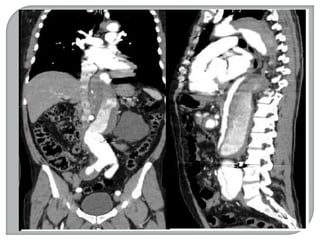

-TOMOGRAFIA COMPUTADORIZADA

 Em 1967, iniciaram-se as 11 pesquisas sobre

reconhecimento de imagens e técnicas de

armazenamento de dados em um computador.

 Em 1971 foi realizado o primeiro teste de um

“SCANNER” do crânio, num hospital de Londres.

 O scanner foi apresentado oficialmente em 1972.

 A.M Comark (Físico norte americano) e Geoffrey

Hounsfield (engenheiro inglês).

 EMI primeira empresa a fabricar o scanner.

Gravadora de discos (Beatles).

 Reconhecidos como TOMÓGRAFOS

COMPUTADORIZADOS.

 Em 1979, estes dois cientistas receberam o

prêmio Nobel.